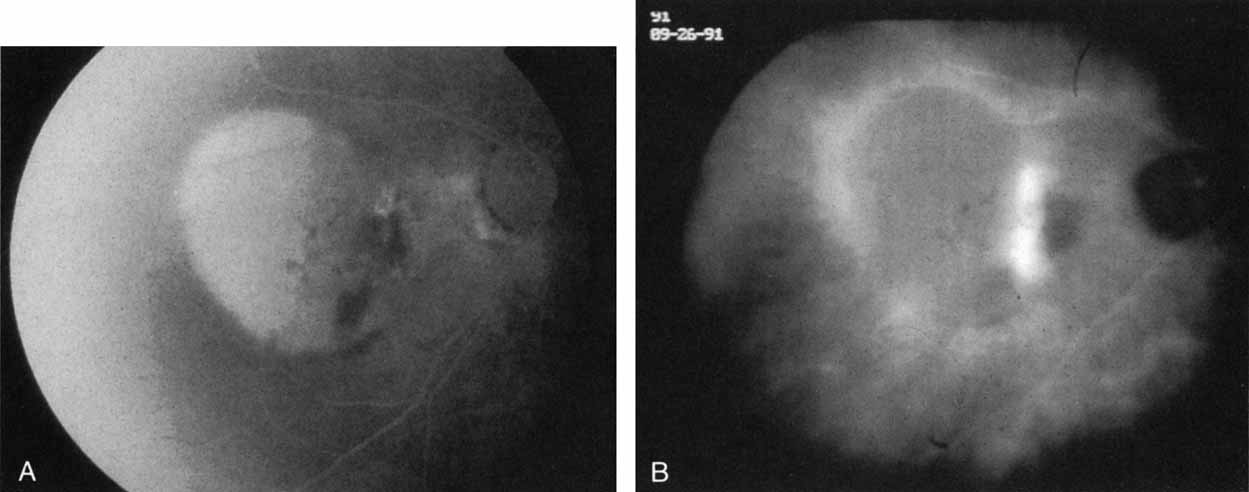

Idiopathic polypoidal choroidal vasculopathy, also known as posterior uveal bleeding syndrome, typically affects darkly pigmented persons who exhibit acute exudative manifestations in the posterior pole, including subretinal hemorrhage and, occasionally, CNV.76,77 ICG angiography facilitates a more definitive diagnosis than fluorescein angiography because it achieves a sharper image of the primary lesion,51,77,78 dilated choroidal vessels terminating in polypoidal or aneurysmal excrescences at the level of the choroid (Fig. 23). These vascular changes account for the secondary exudative and hemorrhagic detachments of the retinal pigment epithelium and neurosensory retina that are characteristic of this disorder. Furthermore, ICG angiography may provide a better means of differentiating the relatively benign aneurysm-like changes at the level of the larger choroidal vessels from CNV, a more devastating secondary manifestation of this chronic disease.79

Fig. 23 A. Clinical photograph of a patient with idiopathic polypoidal choroidal vasculopathy demonstrating the branching lesion at the level of the choroid. There is a more nodular elevation in the inferior macula. A hemorrhagic detachment of the retina is noted temporally in a curvilinear fashion. B. “Green-free” photograph that more vividly demonstrates the branching vascular pattern of this condition. C. High-magnification image of an early-phase indocyanine green (ICG) study reveals filling of the vascular channels at the level of the choroid leading to the polypoidal lesions. Note that the inferior, more elevated lesion, which is nodular on clinical examination, consists of an internal network of branching vessels. D. Late-phase ICG study demonstrates ring-like staining of the small polypoidal lesions. The larger lesion shows intense but nonhomogeneous staining.